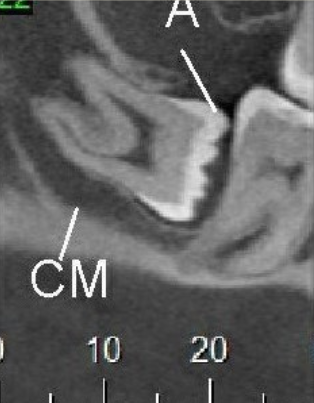

Veja alguns casos de sucesso